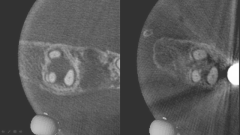

カンガルーテクニック症例1

治療前

治療前 治療後

治療後

◆治療内容

切断された歯肉を再生することを目的とした治療です。 歯間乳頭の剥離は行いません。

◆リスク

・感染リスクが高まる

・瘢痕による審美性の悪化

◆治療費

保険適用外 20,000円 (税別)